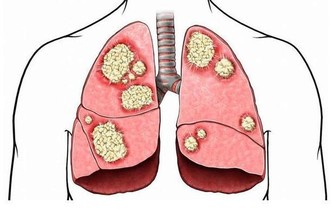

在秋天的時候,因為天氣比較乾燥,而人體排尿會比較少,尿道得不到正常的沖洗,這時候男性朋友就容易出現各種前列腺方面的疾病了,而對於經常吸煙的人來說,肺部也是更容易受傷的,而適當的進補,可以幫助我們防“秋燥”,同時還可以增強體質,健康過一冬。